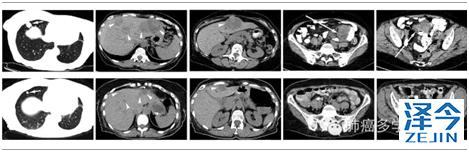

刘学文等通过高通量测序及针对MET基因进行双向测序,在36例肺肉瘤样癌中发现了 8 例 METexon14缺失(发生率22%)。同时报道了1例肺肉瘤样癌接受克唑替尼治疗肿瘤退缩约 80%(见下图)。这 8 例 MET exon14 突变患者的特征:不存在 EGFR、KRAS、BRAF、ALK突变(互斥)。其中1 例合并有 PIK3CA 突变。8 例MET突变中 7 例的肿瘤组织存在腺泡样腺癌成分。【J Clin Oncol. 2015 Jul 27】